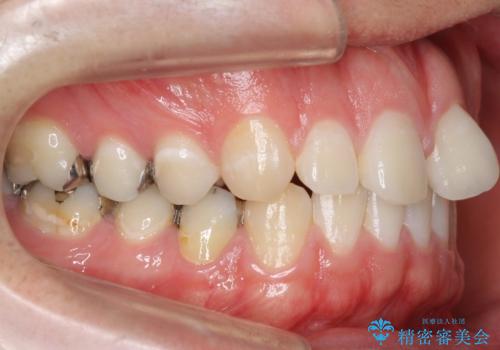

前歯のねじれ 上だけ部分矯正でコストダウン

- 前歯のねじれを部分矯正で治療しました。

奥歯のかみ合わせを変えずに、費用を抑えて短期間に治療したい方におすすめです。

矯正前に、後戻り防止のため上唇小帯の処置を行っています。

奥歯のかみあわせも問題なく、また、下の前歯のがたつきが元からない場合は上の部分矯正が十分可能です。

上下親知らずの抜歯や虫歯処置も矯正前後で行っています。